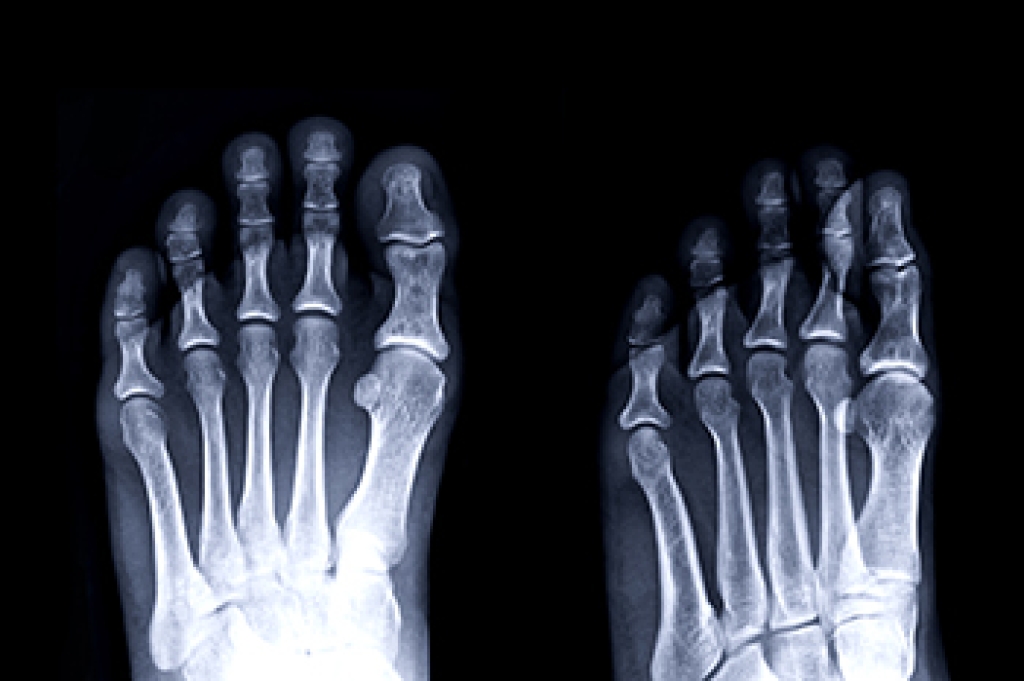

Sever’s disease is also known as calcaneal apophysitis, which is a medical condition that causes heel pain I none or both feet. The disease is known to affect children between the ages of 8 and 14.

Sever’s disease occurs when part of the child’s heel known as the growth plate (calcaneal epiphysis) is attached to the Achilles tendon. This area can suffer injury when the muscles and tendons of the growing foot do not keep pace with bone growth. Therefore, the constant pain which one experiences at the back of the heel will make the child unable to put any weight on the heel. The child is then forced to walk on their toes.